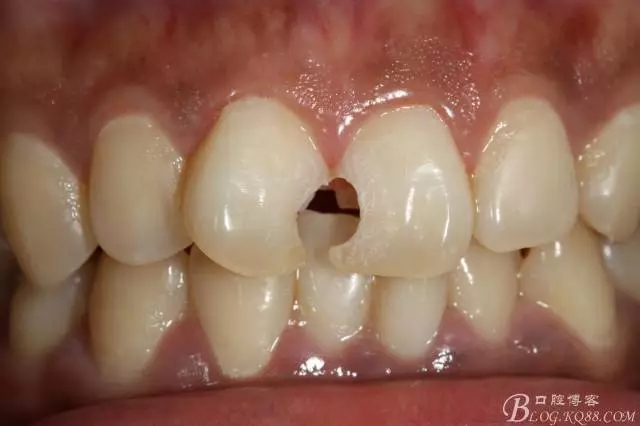

3mz250充填完成即刻照

(2014年9月復(fù)查時(shí)樹脂邊緣明顯做了一次拋光處理,當(dāng)時(shí)就建議做貼面未果??上?這次沒有留得照片)